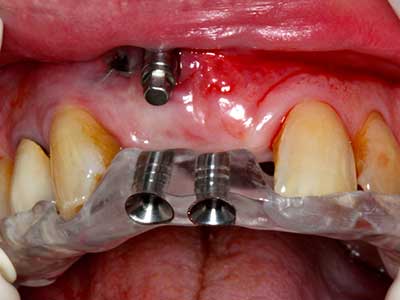

As shown in the past, basically any bone surgery procedure represents a possible indication for piezo surgery. Thus preparation of the mobile segment in distraction osteogenesis (Fig. 23-25) and sandwich osteotomy uses special attachments without endangering the blood supply to the crestal section, which is essential for the success of both techniques (Gonzalez-Garcia, Diniz-Freitas et al. 2008).

For removal of an implant, a vestibular bone cover that is replaced after removal of the implant screw can be prepared to retain the contour of the alveolar ridge.

There are additional applications in sinus surgery. Pathologies and foreign bodies can be removed from the sinus after concentric preparation of a generally trapezoid bone cover in the facial sinus wall. The bone cover is repositioned on conclusion of the intra-antral operation component and secured by wedging or adaptive sutures to prevent dislocation.

Purely orthodontic indications include orthognathic surgery, genioplasty (Fig. 27-30) and orbital decompression in patients with advanced endocrine orbitopathy as a result of Basedow’s disease (Ponto, Zwiener et al. 2014). Piezo devices are also used in maxillofacial surgery and to remove tumours at the base of the skull in various hospitals.